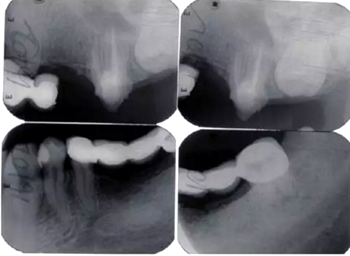

3.影像學(xué)檢查:

全口根尖X線片示鄰面骨嵴頂影像模糊;根管欠填、根充不致密,、未見根管治療影像,、根尖周可見低密度影像(圖2)。

圖2 患者初診時全口根尖X線片